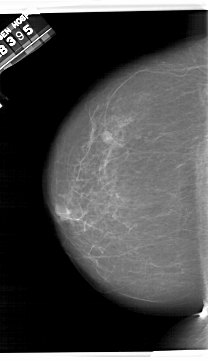

A_1409_1.RIGHT_MLO

RIGHT_MLO LINES 6451 PIXELS_PER_LINE 3736 BITS_PER_PIXEL 12 RESOLUTION 43.5 OVERLAY